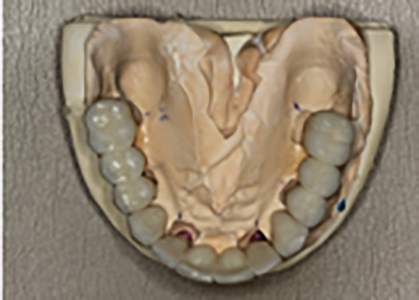

The final treatment plan would require implants in the #16, 14, 12, 22, 24 and 26 positions. The fixed provisional prosthesis would make use of provisional abutments on #17 and 27, 13, 23 and 11. The plan would involve serial extractions and grafting procedures to preserve bone volume in the ideal sites while avoiding any load on the newly grafted sites using strategic teeth to serve as provisional abutments. Patient accepted this solution and agreed to keep teeth #13 and #23. Benefits include cuspid rise occlusion, bone preservation and proprioception (also to minimize the significant risk with adjacent implants in the anterior zone).

- N.B. Existing #17 to be converted to #16, existing #16 to be converted to #15 and 14, existing #26 to be converted to #24 and 25. Lastly #27 will be converted to 26.

- Prepare #17, 27 13, 11 and 23 and provisionalization.

- Extraction of #16, 12, 22 and 26. (Socket grafting #16, and 26 to preserve existing bone volume).

- Immediate implant placement in sites #12, 22, 14 and 24.